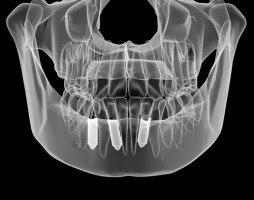

A tooth implant, or dental implant, is a replacement for a tooth root. Usually made from titanium, it is inserted into the jaw to hold a false tooth, bridge or denture in place.

A dental implant is inserted into the jaw under the gum. The implant is usually left to fuse with the jaw bone before a false tooth is fitted. This process is called osseointegration. It produces a secure bond between the tooth implant and the surrounding bone.

The implants themselves are normally concealed beneath the gums. The only visible part of an implant-supported restoration should be the false teeth which comprise the crown, bridge or denture.

A thorough examination and x-rays give a lot of information on the amount of bone you have. In addition it may be recommended that you have a CT scan taken to provide more detail.

A CT (computerised tomography) scan gives the implant dentist a 3D image of the bone volume and shape of your jaws. The dentist can then assess whether the patient is suitable for tooth implant treatment. The scan may also be used to create a surgical guide to accurately place your implant.